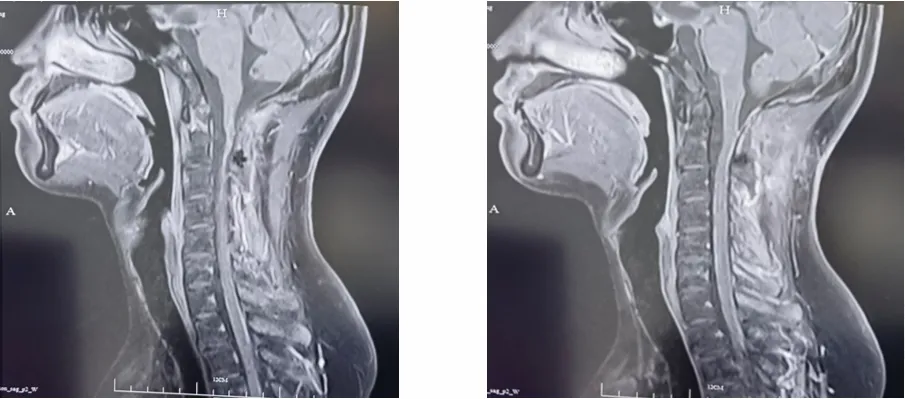

2022年9月15日,头颅MRI提示疾病稳定(SD)。

图4.维持化疗期间头颅MRI检查结果(2022.9.15)

2022年10月14日,行脊髓MRI检查,疗效评价SD。

图5.维持化疗期间脊髓MRI检查结果(2022.10.14)

2023年1月4日、1月6日,复查头颅MRI、脊髓MRI检查,疗效评价SD。

图6.维持化疗期间头颅MRI检查结果(2023.01.04)

图7.维持化疗期间脊髓MRI检查结果(2023.01.06)